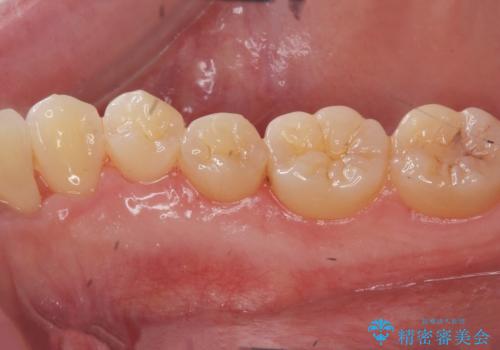

舌のスペースが広くなったと喜んでいただくことができました。

反対側も除去を予定しています。